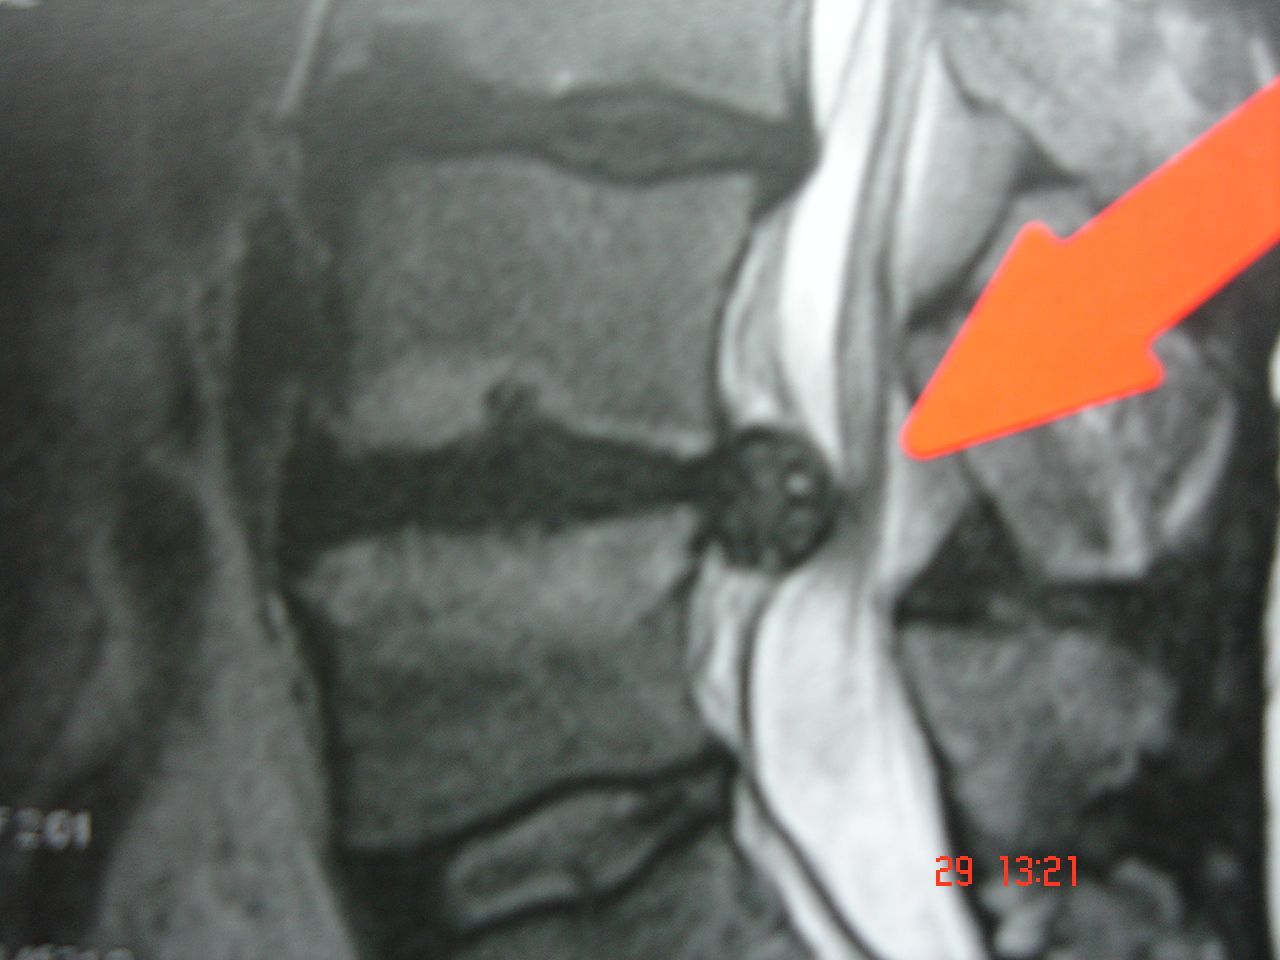

Im apex spine® Center bieten wir Ihnen im ersten Schritt neben einer ausführlichen klinischen und körperlichen Untersuchung zusätzlich eine radiologische Diagnostik mit Röntgen und Kernspintomografie. Abhängig von Ihrem persönlichen Befund stellen wir eine Erfolg versprechende Behandlung für Sie individuell zusammen.

- Magnetresonanztomographie